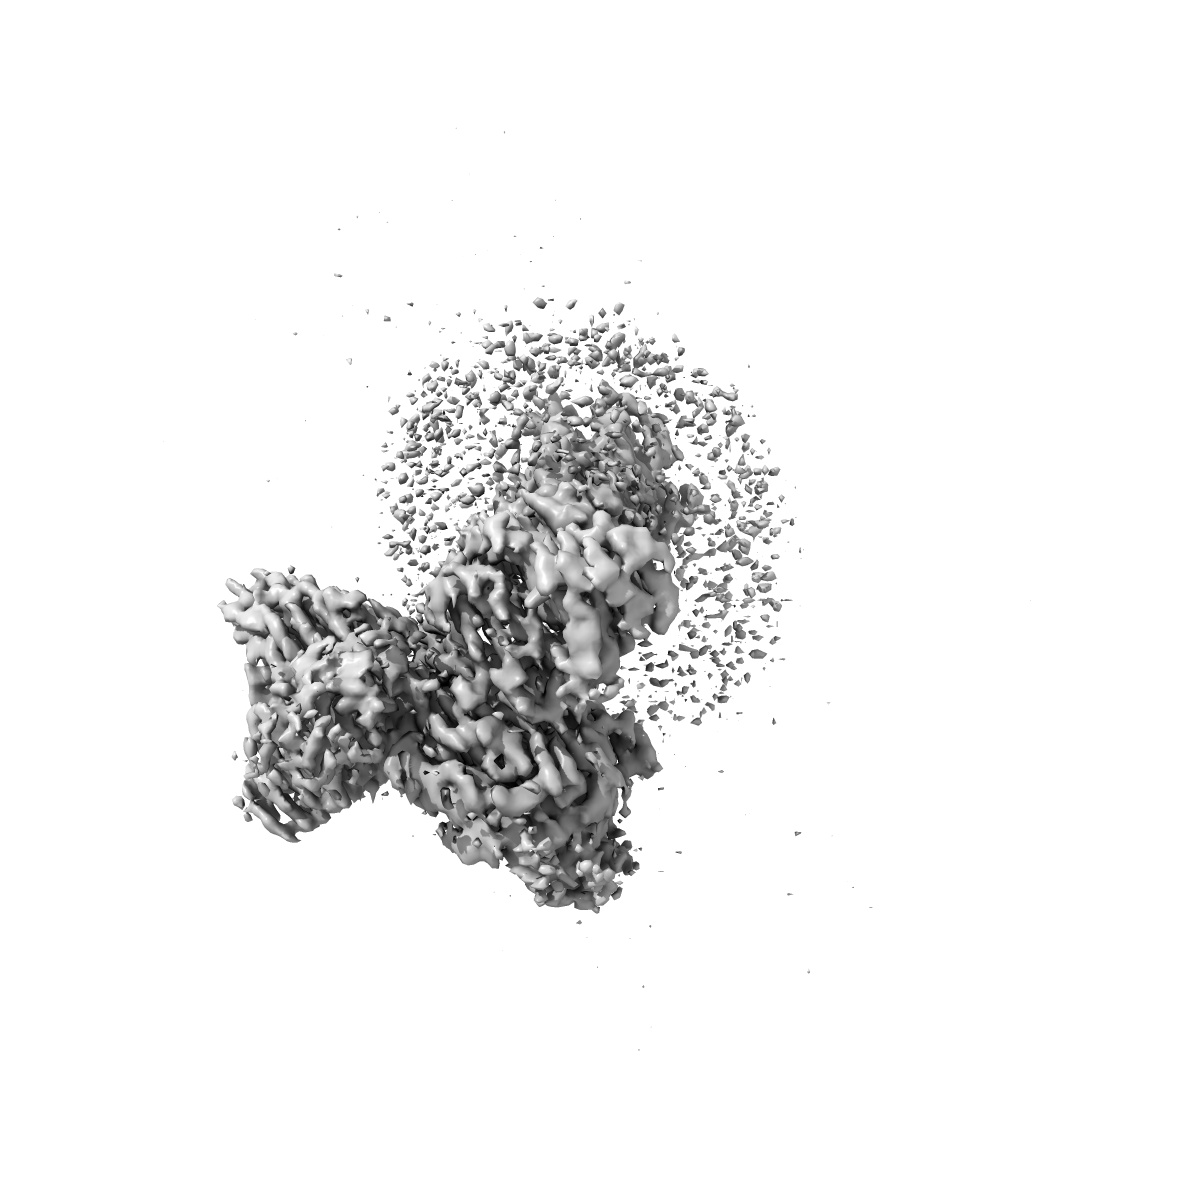

CryoEM structure of somatostatin receptor 4 (SSTR4) in complex with Gi1 and its endogeneous ligand SST-14

Sample: Complex structure of somatostatin receptor 4 (SSTR4) in complex with Gi and its endogeneous ligand SST-14

Fitted models: 7xms